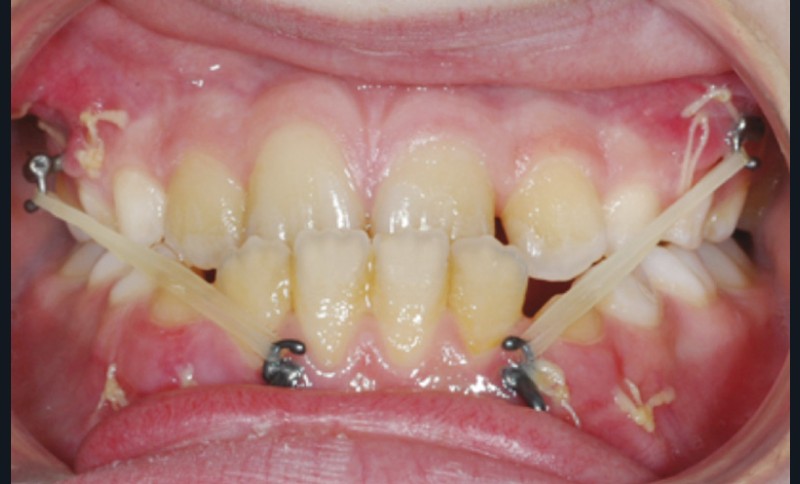

Dès l’évolution des canines mandibulaires, les plaques ont été fixées, et 3 semaines après, malgré une grande sensibilité au niveau du secteur I, la mécanique élastique de classe III a été commencée (fig. 2).